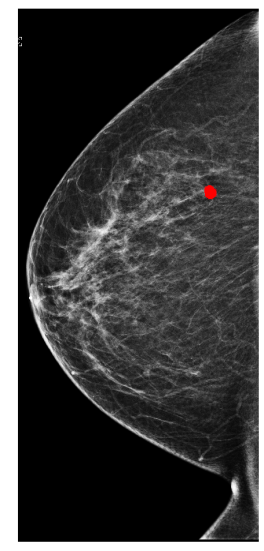

Figure 1: An example of an annotation of a malignant lesion (left) and predictions (right) from a X-101 model on a test set breast.

In Figure 1, we show an annotation and the corresponding prediction using an X-101 model. The model accurately predicts a malignant lesion with high probability (0.99). It also predicts a benign lesion with low probability (0.36) for which there is no ground-truth annotation. These bounding boxes can highlight suspicious regions and help radiologists understand predictions from our models.